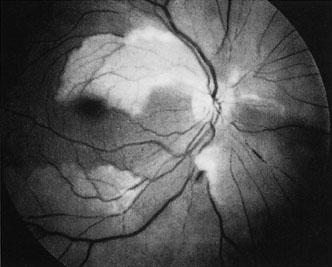

CENTRAL RETINAL ARTERY OBSTRUCTION Central retinal artery obstruction is one of the most sudden and dramatic events seen by ophthalmologists and was described as early as 1859.1 Although there have been numerous clinical and experimental studies of the pathophysiology of central retinal artery obstruction and although these studies have been augmented by the introduction of intravenous fluorescein angiography in the 1960s, the disease still has a relatively poor visual prognosis. The clinical picture is typically striking. Patients present with a sudden painless loss of vision. The appearance of a cherry-red spot in the fundus is characteristic (Fig. 1).2 The cherry-red spot appears because soon after obstruction of the blood flow to the inner retina, the normally transparent retina becomes opaque and blocks the brownish-red color from the underlying choroid, which is still supplied by blood. Because the retina overlying the foveola is relatively thin, however, the normal color of the choroid is still visible in this area.3,4 Although characteristic, the cherry-red spot is not pathognomonic for central retina artery obstruction.5 Sometimes the characteristic cherry-red spot does not develop; there may be only a slight accentuation of the brownish-red color in the foveola.4 It is not known how long it takes this cherry-red spot to appear, but in a primate model, it has appeared as early as 30 minutes after obstruction.6 An afferent pupil defect is usually present.2 With obstruction, virtually all eyes have narrowing and irregularity in the arteries and there is frequently an irregularity in the caliber of the retinal veins.2,4,6,7 Segmentation (boxcarring) of the blood column frequently develops; this segmentation is particularly noticeable in the veins and can be seen as a to-and-fro movement of the blood elements.3,4 Retinal hemorrhages, however, are not characteristic of central retinal artery obstruction.7 With time, the retinal opacity diminishes, generally leaving an optic nerve that is atrophic (Fig. 1). Frequently, thinned retinal arteries and veins also remain.7,8 No foveolar light reflex is evident, and a finely pigmented appearance of the macula is typical.7 In some cases, arterial collaterals develop at the optic disc.9–11 Rarely, anatomoses that exist between the central retinal artery and the ciliary arteries become visible as preretinal loops (Nettleship collaterals) after an occlusion at the edge of the disc.12,13,378In approximately 20% of patients, an embolus is evident somewhere in the arterial system.14 Emboli are discussed later. Intravenous fluorescein angiography is useful in showing the details of the abnormal circulation of a central retinal artery obstruction (Fig. 1). The principal abnormality is the delay in the appearance of the dye in the central retinal artery and its branches.2 Rather than the central retinal artery and its branches filling rapidly, considerable time may elapse before the entire arterial system is filled.15 The filling of the retinal arteries is often abnormal, with the fluorescein partially filling an artery (a dye front) or hugging the vessel wall, as in normal venous filling.15 Segmentation of the blood column is often well defined on fluorescein angiography.15 Venous filling is usually slowed and occasionally the dye does not progress beyond laminar flow during the study.14 In approximately 10% of eyes that have central retinal artery obstruction, there are abnormal choroidal filling defects, reflecting posterior circulation obstruction. These defects can occur even in patients who appear to have a typical central retinal artery obstruction.14 Leakage of dye from the vessel walls is not normally seen except at the site where an embolus lodges within a retinal artery.16 With time, the flow within the artery and its branches is reestablished and the appearance of the intravenous fluorescein angiogram may return to normal. The electroretinogram (ERG) is usually abnormal in central retinal artery obstruction. The b-wave is reduced, indicating a marked abnormality in the circulation of the inner retina.17,18 The a-wave, indicating normal photoreceptor function, is preserved or accentuated. There does not appear to be a good correlation, however, between the extent of b-wave abnormality and the degree of retinal function,3 although Yotsukura and Adachi-Usami420 reported that the b-wave amplitude increased with visual improvement. The photopic negative response (PhNR) shows severe depression in this condition reflecting the significant loss of the ganglion cells and their axons.377 The electrooculogram may be either normal or abnormal. Visual field defects are usually profound but either occasionally a small portion of the temporal peripheral visual field remains or the patient has a large central scotoma.3 The onset of obstruction occurs most often between the hours of midnight and 6 AM, with the second most common period being between 6 AM and noon.2 Most patients with central retinal artery obstruction complain of a sudden loss of visual acuity in the affected eye; most of these patients present with visual acuity ranging from finger-counting to light perception.14 Only about 5% of patients have visual acuity of no light perception and most of these have involvement of the posterior ciliary circulation, which can be seen on either intravenous fluorescein angiography or electrophysiology.14 Without a partial central retinal artery obstruction or a spared cilioretinal artery (to be discussed), it is unlikely that any patient will have initial visual acuity better than finger-counting.14 With or without treatment, most eyes retain visual acuity of finger-counting to light perception. Patients with a spared cilioretinal artery do not seem to have a follow-up visual acuity that is significantly different from those without a spared cilioretinal artery.14 Central retinal artery obstruction is caused by the disruption or cessation of blood flow to the central retinal artery, its branches, and the retinal layers supplied by those vessels. The inner two thirds of the retina derives its blood supply from the central retinal artery and its branches; the outer third of the retina is supplied from the choroidal circulation.19–21 The central retinal artery and its branches function as an end artery, and with the exception of a few anastomotic connections between the retina and the ciliary circulation at the optic disc, there are no other anastomoses.19 No intrinsic retinal vessels are present in the fovea because the inner retinal layers are not present in this area.19 Histopathologically, when a central retinal artery obstruction occurs, the retina initially becomes edematous. With time, all the retinal layers supplied by the central retinal artery and the artery's branches, including the nerve fiber layer, ganglion cells, inner plexiform layers, and the inner portion of the inner nuclear layer, are lost.20 In trypsin digest preparations after obstruction of the central retinal artery, the greatest change is in the capillary bed,22 where extensive ischemic changes take place. Usually, little attempt is made to repair the retina with gliosis or neovascularization.20 The most common site of obstruction of the central retinal artery is at the level of the lamina cribrosa.20 Clinically, it is possible to examine the blood flow velocity in the central retinal artery in a noninvasive manner, using a variety of techniques.21 The most useful appears to be color Doppler imaging, providing simultaneous Doppler and B-scan ultrasound images of the optic nerve head, which primarily represents flow in the central retinal artery.23 Studies using this technique demonstrate a marked reduction of or no blood flow in the central retinal artery with an acute central retinal artery occlusion that returns to normal with time.24 Characteristics of the retinal blood flow can be measured clinically with retinal Doppler velocimetry.385 This is an instrument that can measure the blood column diameter, the centerline blood velocity, and the blood flow in major retinal vessels. However, when evaluating the blood flow in the optic nerve, choroidal, and retina, the Doppler laser flowmetry is more sensitive to the blood flow in the superficial layers than in the deeper layers.410 Masaoka and colleagues384 studied the hemodynamic changes in the retinal circulation with a scanning laser ophthalmoscope and intravenous fluorescein angiography. This technique allows the assessment of erythrocyte velocities and movement with high resolution continuous images and is a useful technique for the evaluation of hemodynamic changes in vascular occlusions. Analysis of the retinal nerve fiber layer by one of the confocal laser scanning tomography techniques can provide information about a central retinal artery occlusion. Foroozan and co-workers383 studied patients with a central retinal artery occlusion within 1 week of occlusion with a scanning laser polarimeter. Diffuse attenuation of the retardation of the nerve fiber layer surrounding the optic nerve was seen in all eyes studied. Four patients were scanned in follow-up at intervals ranging from 1 week to 6 weeks; all had unchanged studies.383 Optic coherence tomography (OCT) of an acute central retinal artery occlusion shows a slight increase in the thickening of the retina and reflectivity of the inner layers of the retina that correspond to the opacity seen clinically (Fig. 1).409 With time, the disc becomes atrophic and the retina thinner. Experimental studies of central retinal artery obstruction in the cat25 and the rhesus monkey26–28 have increased our understanding of arterial obstruction. The most clinically relevant finding is that there is a period in which a total lack of blood flow (ischemia) to the inner retina can be tolerated; that is, if the blood flow is not obstructed longer than this period, visual function may return to normal. This critical time in the cat eye is 90 minutes,25 and in the young, healthy rhesus monkey it is 100 minutes26–28—any longer than this and the histologic changes are irreversible and the animal has permanent visual loss. Hayreh and co-workers379,380 have repeated this experiment to determine how long the retina can survive central retinal artery occlusion in middle-aged and elderly rhesus monkeys, a situation that might be more applicable to the human situation where most occlusions occur in older patients. That study showed that an occlusion of less than approximately 100 minutes produced no permanent damage and that an occlusion of longer than 240 minutes produced massive and irreversible retinal damage. It is not known why the older monkeys had a longer retinal survival time with occlusion of the central retinal artery than younger monkeys. Because there is no evidence that the monkey and the human have different retinas,379 the studies by Hayreh and co-workers have implications for studies that attempt to treat central retinal artery occlusion. Any treatment of this condition will almost certainly have to be initiated within 100 to 240 minutes, assuming the occlusion is total, or the patient will likely have permanent damage to the retina, regardless of treatment. On average, central retinal artery obstruction occurs in patients who are in the fifth or sixth decades of life, with the age range varying from 17 to 84 years. Fewer than 10% of patients are younger than 30 years of age.14,29,30 In some cases, the cause of central retinal artery obstruction is relatively clear, such as when due to a visible embolus. In other cases, however, especially when found in association with a systemic disorder such as diabetes, the association is less clear. Table 1 lists some of the conditions associated with central retinal artery occlusion. Arteriosclerosis is probably the most commonly associated systemic condition. With the progressive buildup of subendothelial atheromatous material, the lumen of the central retinal artery becomes narrowed over time and eventually may become occluded.20 This association is inferred because most patients with central retinal artery obstruction are in the fifth to sixth decades of life, when atherosclerotic changes are expected. TABLE 1. Conditions Associated With Retinal Arterial Obstructions